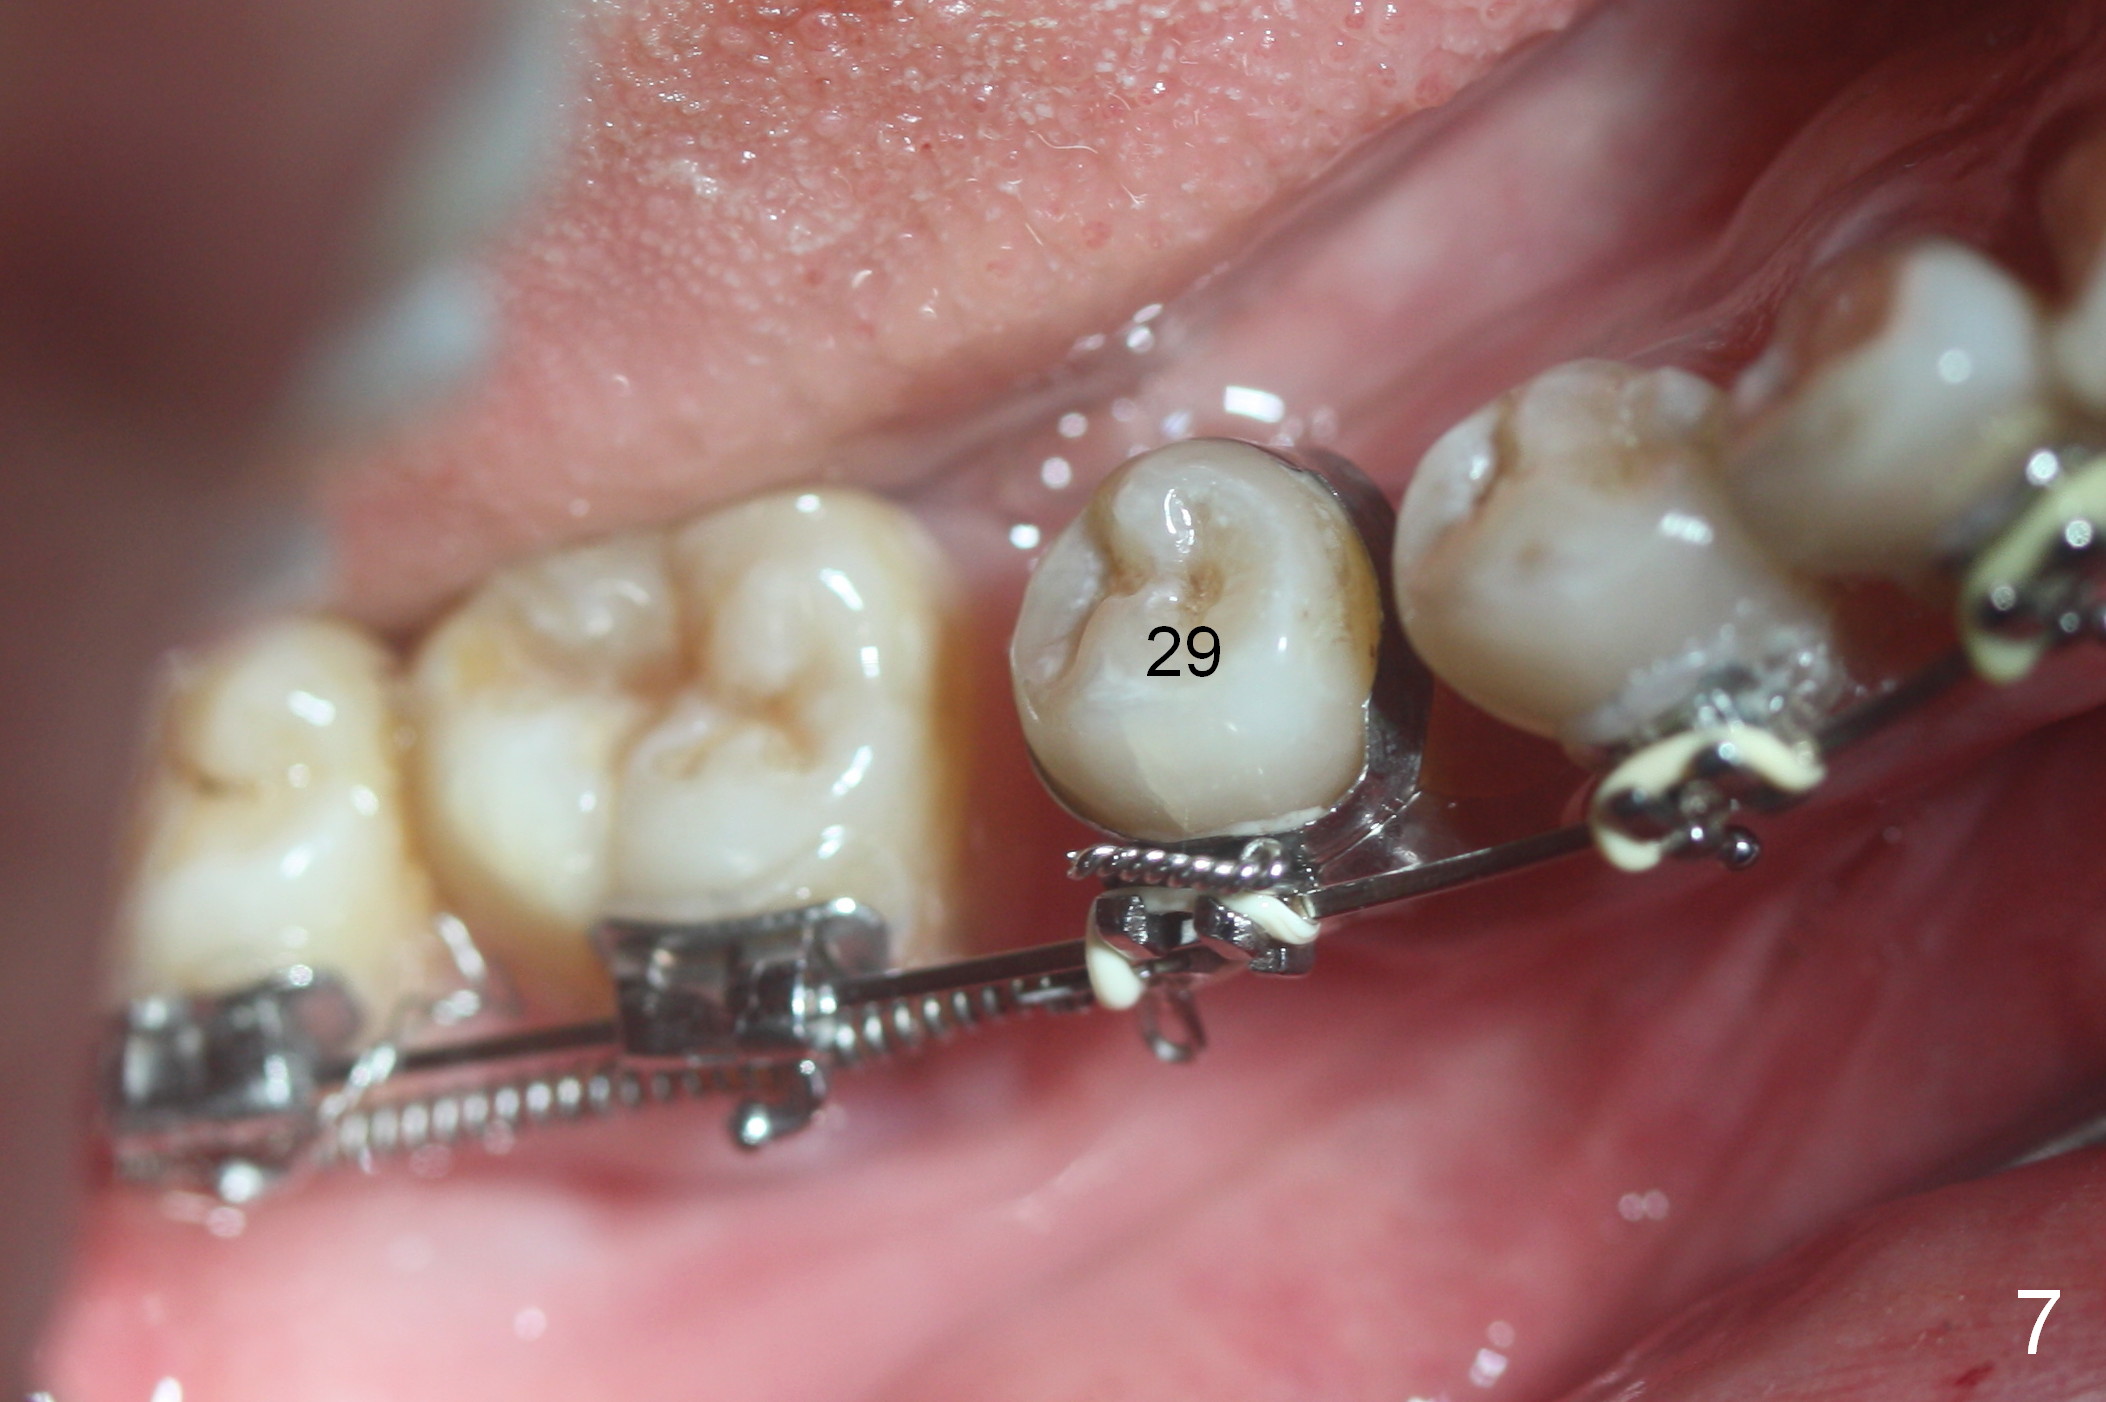

A 47-year-old lady has lost the lower right 1st molar for long time; with reduction of the buccolingual width (Fig.1) and mesiodistal width (Fig.2,3). With regional orthodontic appliance (Fig.4) for 3 months, the tooth #29 has started being distalized (Fig.5). One month and a half later, the tooth #26 starts to shift labially. Power chains and then closed coil spring are placed between #29 and 32. #29 distalization is slow (Fig.7) with closure of the diastema between #31 and 32 (Fig.8, as compared to Fig.1,3). Seven months post banding, a 10 mm miniimplant is placed distobuccal to the tooth #32 (Fig.6); the same 12-mm closed spring is stretched distal by ~ 6 mm (Fig.8 between arrowheads). Two months later, #29 is more distalized (Fig.9 tilted) with bone deposit mesially (*) and coronally (^). A .018' stainless steel wire is installed with an open coil spring placed between #28 and 29 (Fig.10 (^),11). Note #29 rotation (Fig.11). To solve the tilting, a power hook (Fig.12 black) will be clamped to a .016x.016 wire (red), while the closed spring is lowered and attached to the power hook (Fig.12 white). Take photos after removing the existing wire occlusally to show the alveolar width change. When the wire is placed, make sure that the distal wings of #29 bracket is fully engaged to reduce the tooth rotation. Make occlusal adjustment on #31 and 32 to reduce anterior open bite.